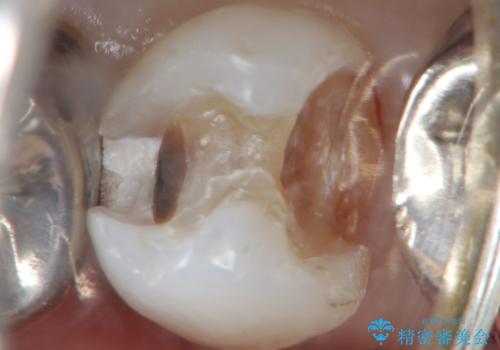

精査したところ、左下の小臼歯(左下5)の銀の詰め物の下に大きなう蝕を認めました。

患者様のご希望により、セラミッククラウンにより可及的にう蝕除去後の補綴及び歯並びの改善を行いました。